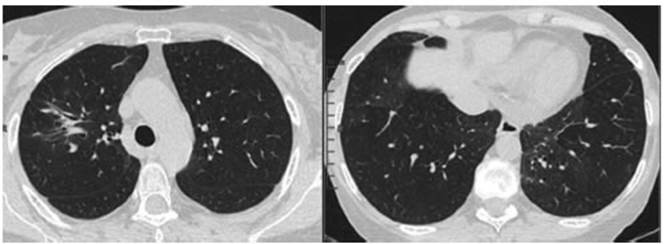

a dos meses de tratamiento, TC 8/03/2022 (Figura 3): Franca

reducción de tamaño de la consolidación en el

vértice derecho y desaparición del resto de los infiltrados en el

parénquima pulmonar.